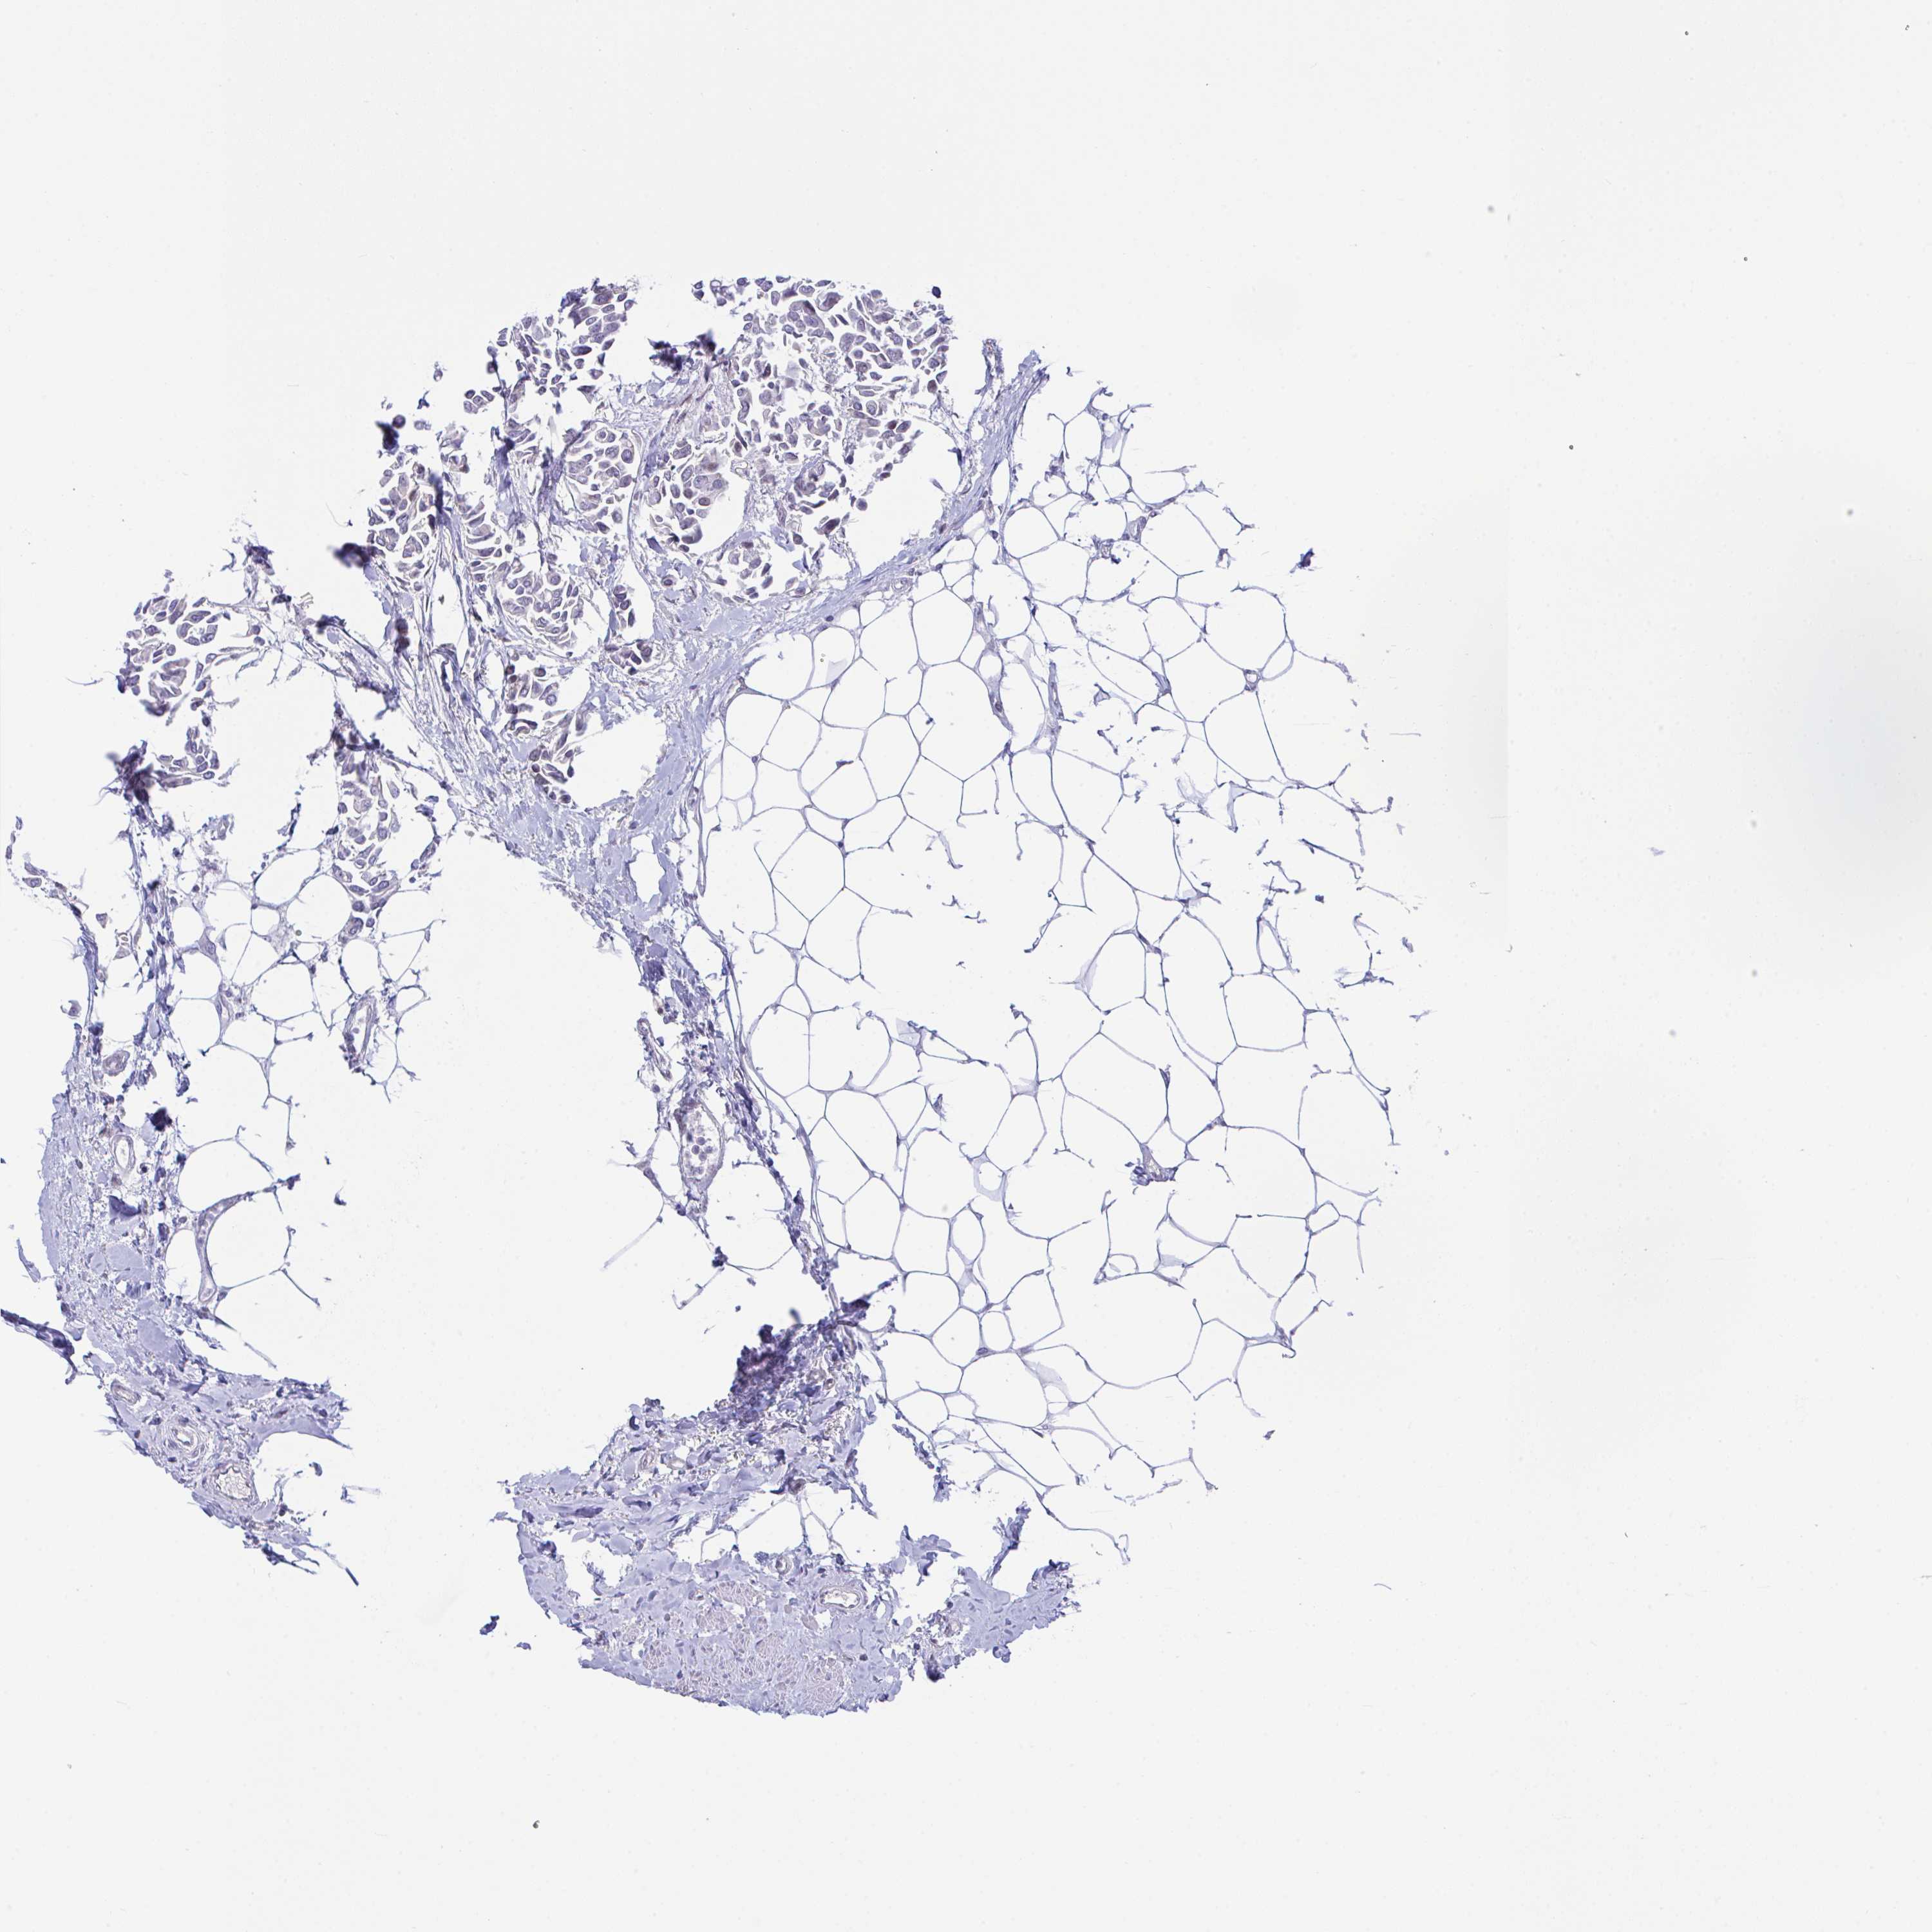

CANCER BREAST CANCER Show tissue menu

BRCA TCGA BRCA VALIDATION PROTEIN EXPRESSION